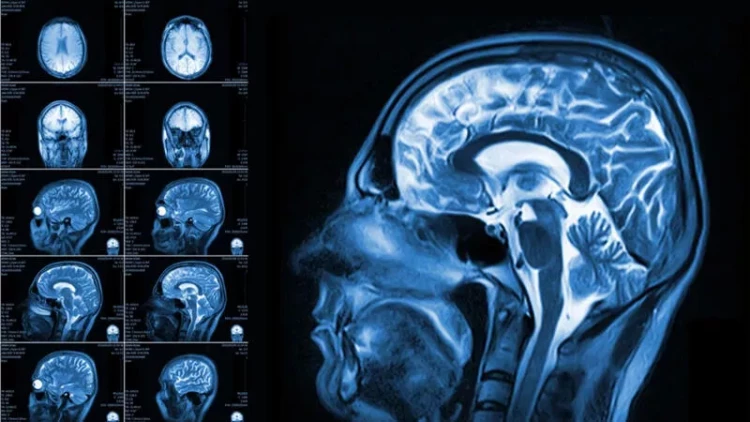

Beynimiz haqqında yeni kəşf: Gördüyünə deyil, gözlədiyinə inanır

İnsan beyninin sirrlərlə dolu olduğu çoxdan məlumdur, lakin son elmi araşdırmalar bu mürəkkəb orqanın işləmə mexanizminə dair daha bir maraqlı həqiqəti üzə çıxarıb. Məlum olub ki, beynimiz gördüklərini deyil, gözlədiklərini daha çox əsas götürür. Yəni insan beyni sadəcə müşahidə etmir, aktiv şəkildə gələcək hadisələri proqnozlaşdırmağa çalışır.